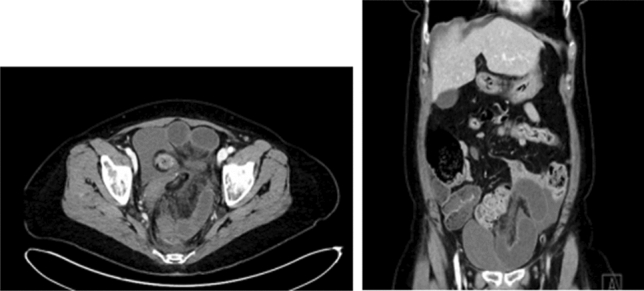

Methods: We present a 72-year-old male with prior radical cystectomy and neobladder creation complicated at the time by neobladder-cutaneous fistula and wound infection requiring revisional surgery and incisional hernia repair with mesh. He developed a large recurrent incisional hernia and underwent open hernia repair with bilateral anterior component separation, extensive lysis of adhesions, removal of prior mesh, and placement of a biologic mesh (Strattice™ RTM) in an underlay and onlay fashion. Intraoperatively, the defect measured 20 cm long by 14 cm wide. Postoperatively, he was treated for neobladder infection and CT cystogram found no extravasation from the neobladder. He presented to the emergency department 6 weeks after surgery with spontaneous partial midline wound dehiscence, with exposure of the onlay mesh and drainage of clear fluid, which was confirmed to be urine by fluid creatinine level. Repeat CT scan demonstrated a filling defect at the anterior wall of the neobladder with contrast leaking into a contained collection interposed between the anterior abdominal wall and the underlay mesh, extending superiorly between the small bowel loops and dehiscence of the midline abdominal wound. The patient was treated with a course of antibiotics and indwelling Foley catheter and bilateral nephrostomy tubes for urine diversion.

Results: Three months later, repeat CT cystogram demonstrated resolution of the leak and the nephrostomy tubes and Foley catheter were removed. The patient has continued daily wound care with significant reduction in size of the midline wound and increasing granulation tissue around the onlay mesh. He has not required further admissions to hospital and there has been no hernia recurrence so far.